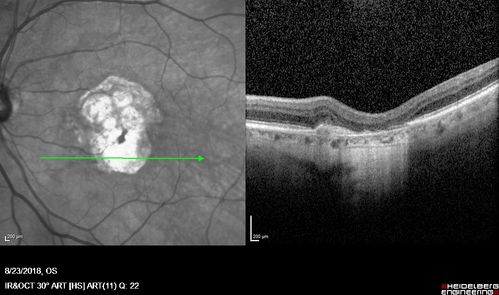

Outer Retinal Tubulation

78 year old man chronic wet AMD - 20/200

Outer Retinal Tubulation - Disciform Scar